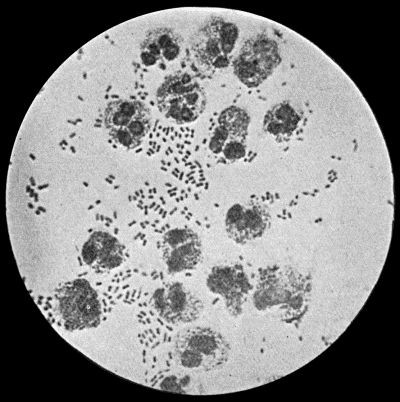

Fig. 2.—Staphylococcus aureus in Pus from case of Osteomyelitis. × 1000 diam. Gram's stain.

Staphylococcus Aureus.—This is the commonest organism found in localised inflammatory and suppurative conditions. It varies greatly in its virulence, and is found in such widely different conditions as skin pustules, boils, carbuncles, and some acute inflammations of bone. As seen by the microscope it occurs in grape-like clusters, fission of the individual cells taking place irregularly (Fig. 2). When grown in artificial media, the colonies assume an orange-yellow colour—hence the name aureus. It is of high vitality and resists more prolonged exposure to high temperatures than most non-sporing bacteria. It is capable of lying latent in the tissues for long periods, for example, in the marrow of long bones, and of again becoming active and causing a fresh outbreak of suppuration. This organism is widely distributed: it is found on the skin, in the mouth, and in other situations in the body, and as it is present in the dust of the air and on all objects upon which dust has settled, it is a continual source of infection unless means are taken to exclude it from wounds.